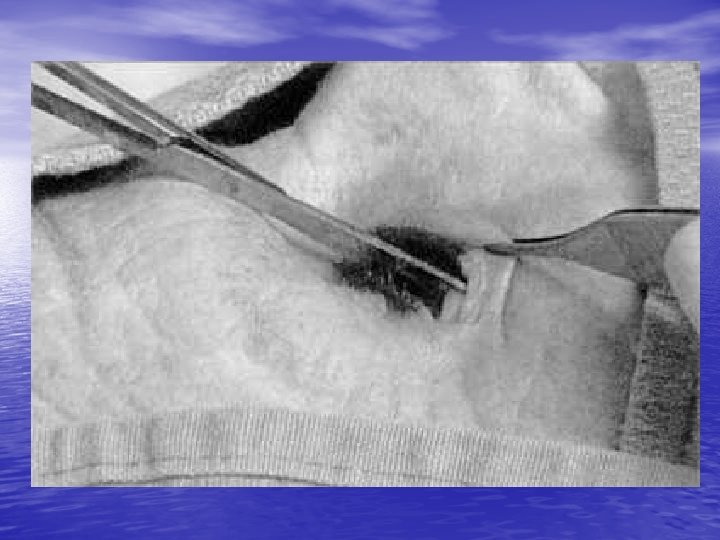

Retrobulbar Hemmorhage: • Hemmorhage in potential space surrounding • • globe may increase intraorbital pressure and cause CRAO. Symptoms=proptosis, visual loss, increased IOP Signs= CRAO Dx= above + orbital CT scan Tx=immediate optho consult, IV mannitol +/lateral canthotomy or anterior chamber paracentesis

Complications: • Infection, hemmorhage, injury to globe • Rare • Canthotomy wounds heal well without suturing or significant scarring